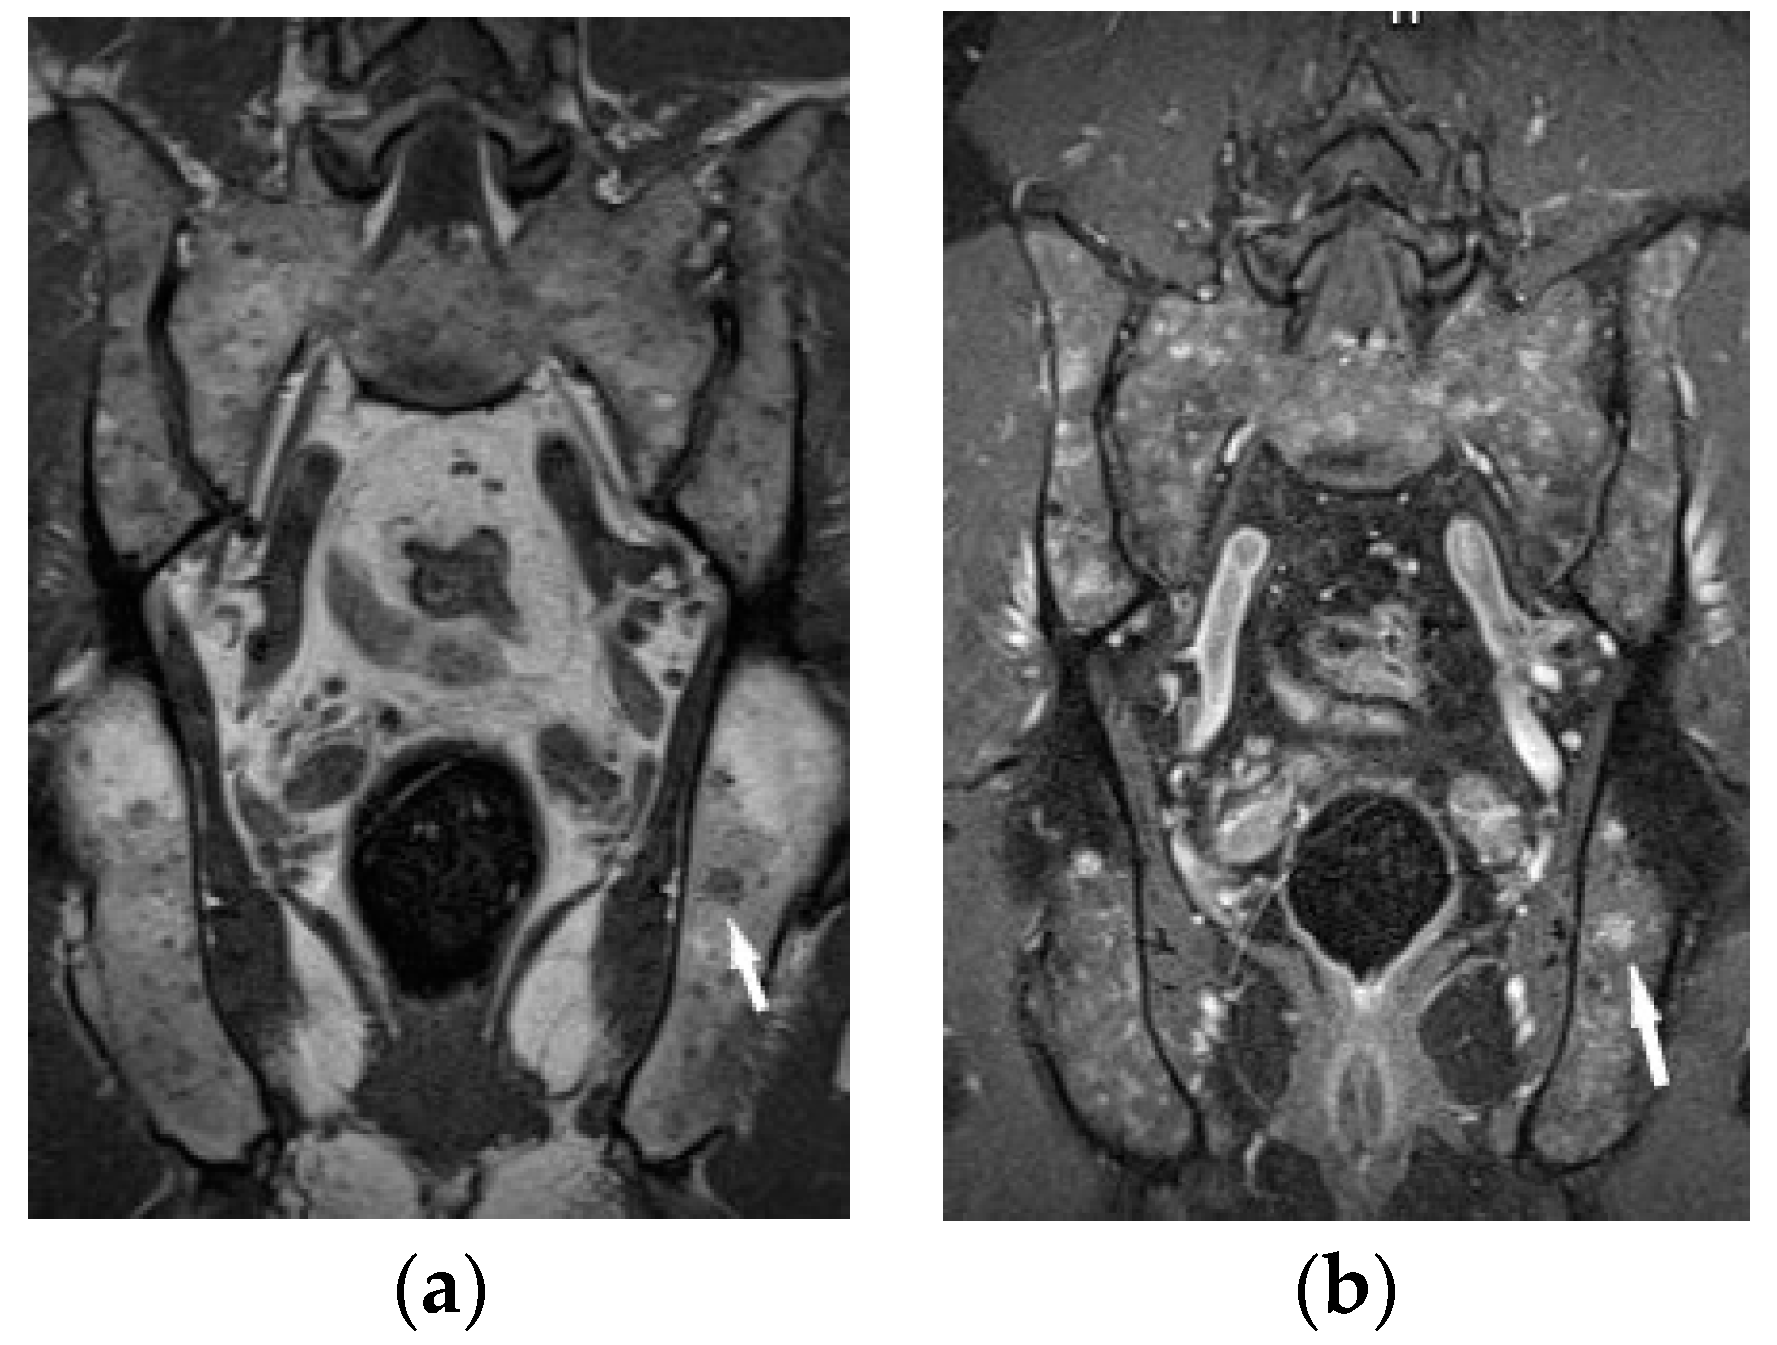

Bone marrow sarcoid foci are hypointense on T1-weighted images and hyperintense on T2-weighted and STIR image, with the same appearance as metastases, multiple myeloma or lymphoma [19] (Figure 8a,b). In T2-weighted images, lesions in sarcoidosis of the bone marrow may also show low and intermediate signal intensity, with signal being higher in STIR images [15].

Figure 8. MRI of the pelvis. T1-weighted image, coronal plane (a), T1-weighed image with fat saturation and with contrast administration (b) shows multiple hypointense bone marrow lesions (a) with contrast enhancement ((b), white arrows).